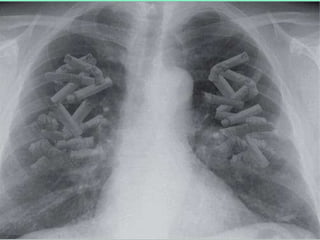

Pulmão normal Pulmão de fumante

Câncer de pulmão

90% dos casos de Câncer de pulmão são em fumantes

Tabagista pesado (> 2 maços/dia) tem risco 30x maior  de câncer de pulmão que o não-fumante